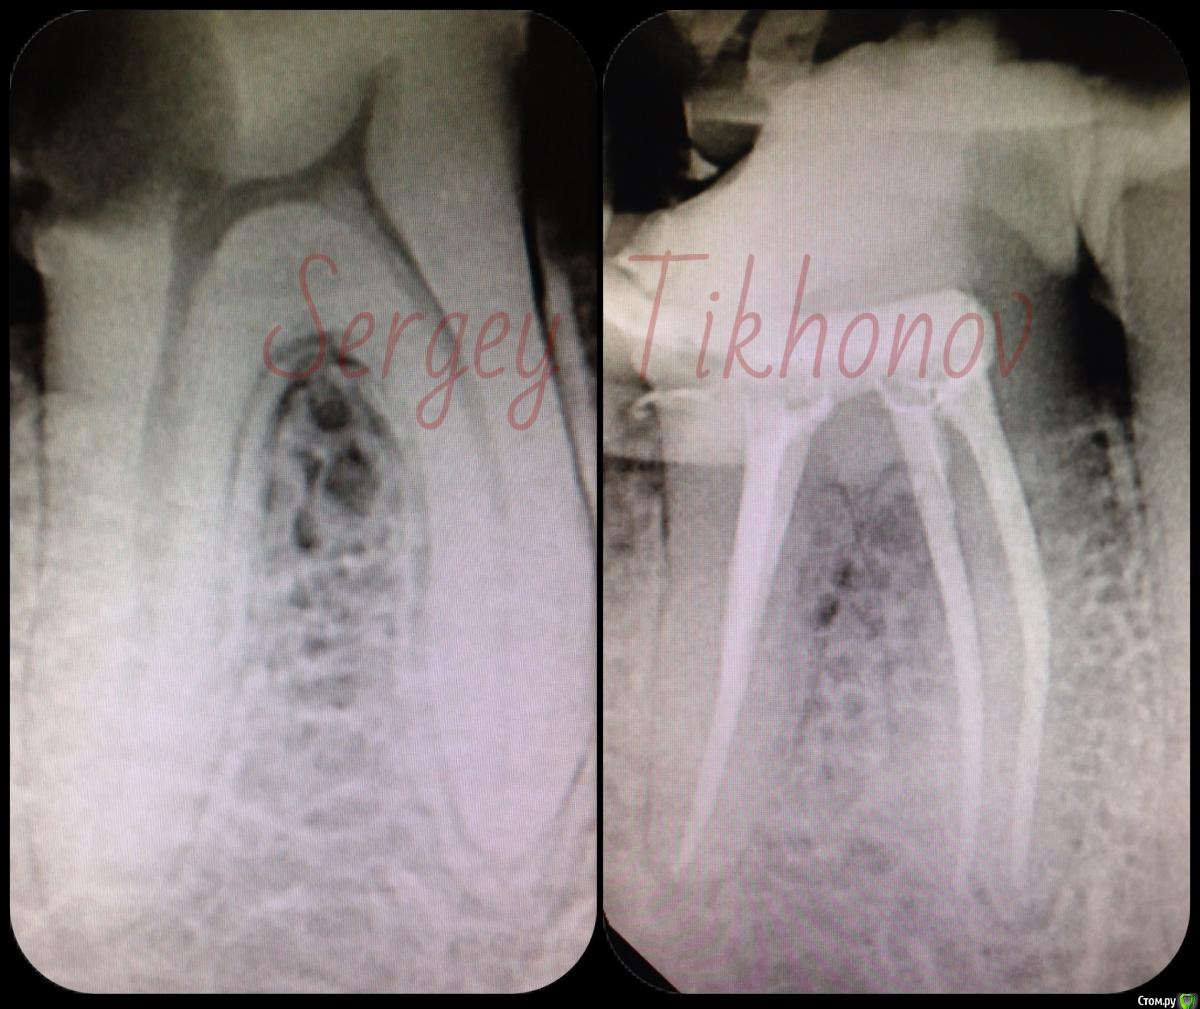

SSTi Опубликовано 22 января, 2015 Автор Поделиться Опубликовано 22 января, 2015 Вот нашел. Может выкладывал уже. Но вроде нет. Любимые нижние премолярки) 5 Ссылка на комментарий

Shaid Опубликовано 24 января, 2015 Поделиться Опубликовано 24 января, 2015 Латерали класс) 2 Ссылка на комментарий